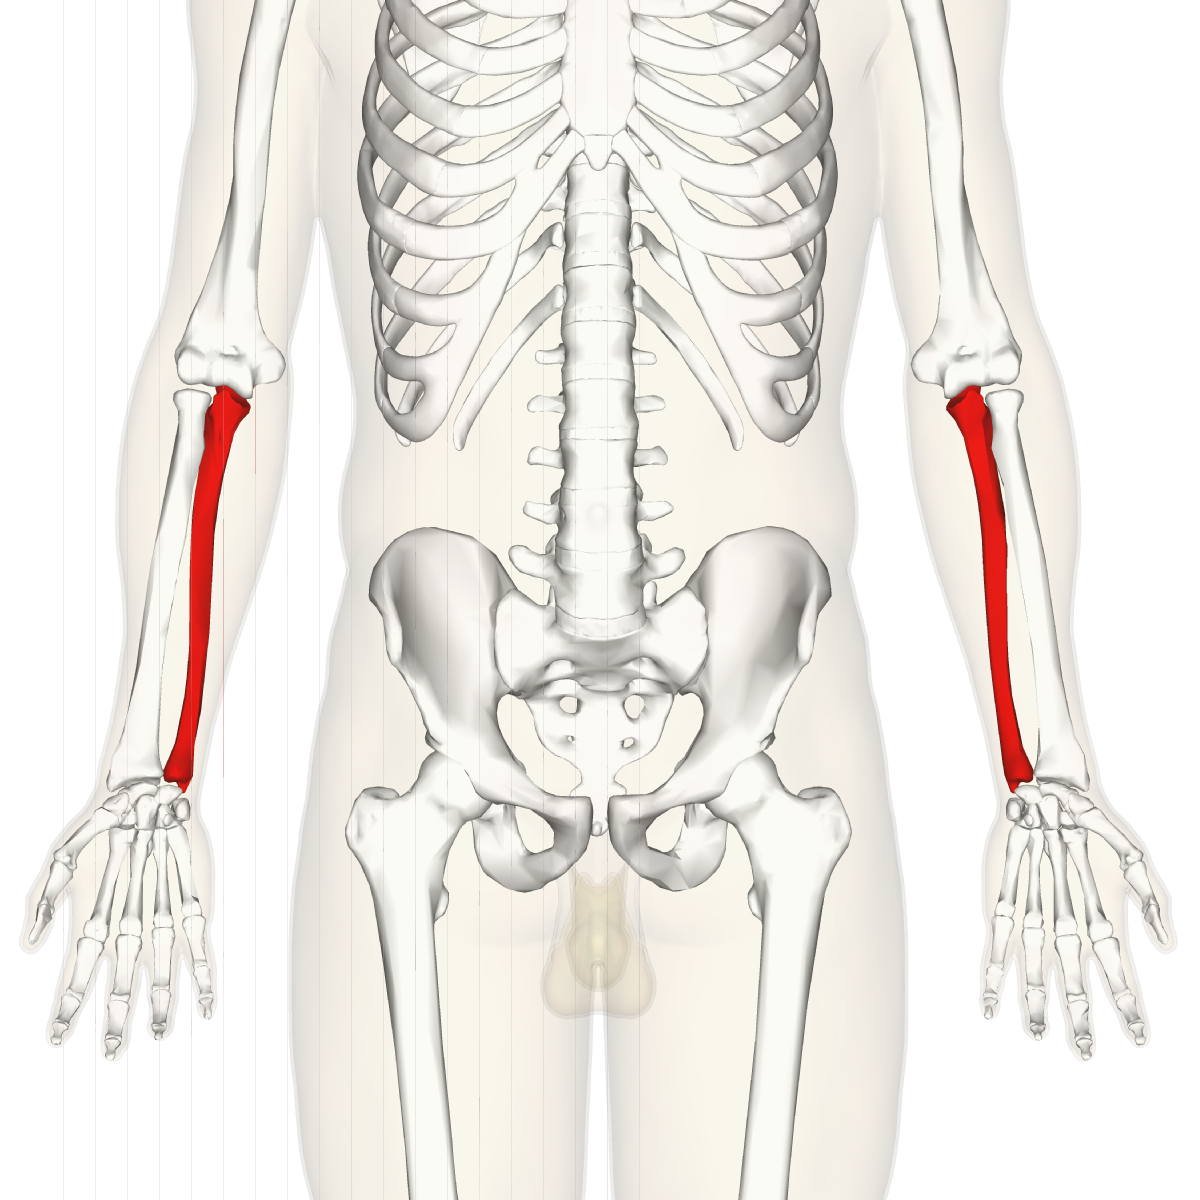

What is this region?

Ulna